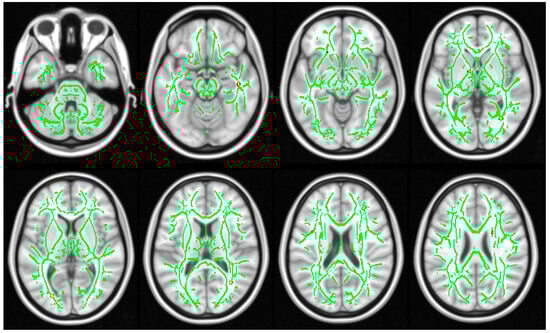

3.3. DTI Results

2.3.3. Statistical Analysis